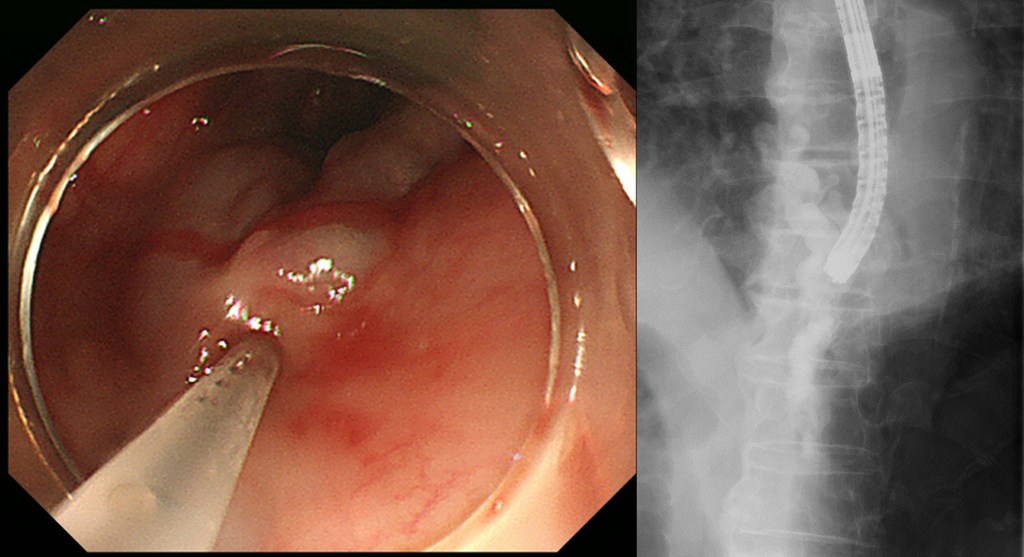

As liver disease progresses, the liver gradually hardens, leading to cirrhosis. Patients with cirrhosis suffer from various complications such as hepatocellular carcinoma, ascites, hepatic encephalopathy, jaundice, and esophagogastric varices. We provide treatment for these complications according to each patient's condition, such as administration of branched-chain amino acid preparations, diuretics, laxatives, zinc preparations, ascites puncture drainage, and albumin preparations. To prevent bleeding from esophagogastric varices, we perform endoscopic variceal ligation (Figure), endoscopic variceal sclerotherapy (Figure), and retrograde transvenous embolization with balloon occlusion in cooperation with the Department of Radiology. In case of rupture of varicose veins, we are ready to respond urgently.

Figure 1: Endoscopic varicocele ligation

Figure 2. Endoscopic variceal sclerotherapy. Inflow of sclerosing agent into esophageal varices.